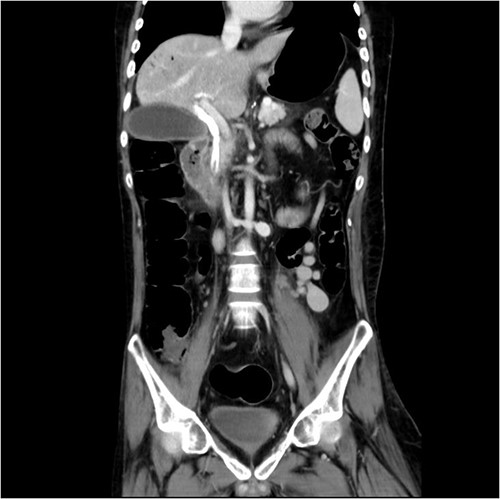

Initial laboratory findings revealed significant hyperbilirubinemia, liver enzyme elevation and mild PT prolongation. Abdominal computed tomography showed a CBD stone caused obstruction, resulting in upstream biliary dilatation and acute cholecystitis (Fig. 1). Besides, small caliber of inferior vena cava, splenic vein, and right iliac veins with thrombosis and prominent collaterals formation was also shown on the image.

Abdominal CT revealed CBD stone resulting in upstream biliary dilatation and acute cholecystitis.